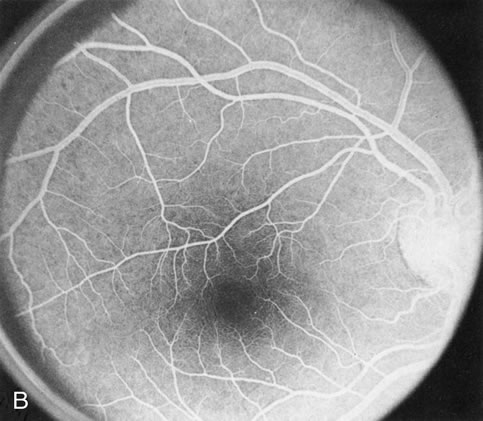

Central Areolar Choroidal Dystrophy

Although central areolar choroidal dystrophy (CACD) and peripapillary (pericentral) choroidal dystrophy are not generalized, but rather localized disorders, they are discussed here as part of the choroidal dystrophies because the angiographic findings are similar.

In CACD the bilateral macular lesions are solitary, circumscribed, and circular or ovoid in shape. They are unassociated with other findings such as drusen or flecks. FA will confirm the well-circumscribed area of choriocapillaris atrophy and further document that there are no associated findings that would lead to secondary choroidal atrophy in disorders such as age-related macular degeneration, Stargardt's fundus flavimaculatus, or dominant drusen of Bruch's membrane11 (Fig. 7 A and B).

Fig. 7. Central areolar choroidal dystrophy. The presence of choroidal atrophy in this well-circumscribed macular lesion (A) is confirmed by persistent visualization of the larger choroidal vessels as seen on angiography (B). Peripapillary (pericentral) choroidal dystrophy. The areas of choroidal atrophy are well-demarcated and contrast with the areas of normal choroid (C, D). Crystalline retinopathy (of Bietti). The areas of choroidal atrophy correspond to areas of the retina where crystals are not present (E, F).

Peripapillary (Pericentral) Choroidal Dystrophy

Peripapillary choroidal atrophy radiates from the optic nerve along the temporal vascular arcades. The macula is affected later in the course, and this is usually responsible for the onset of visual symptoms. FA shows the choroidal atrophy and the early macular changes (Fig. 7C and D).